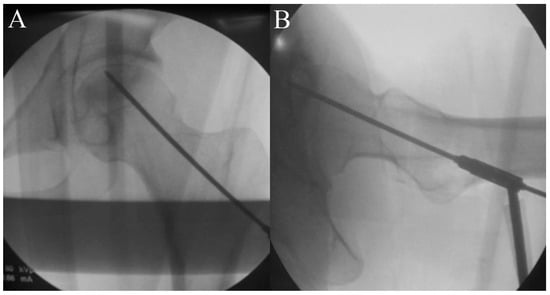

2.5. Procedure